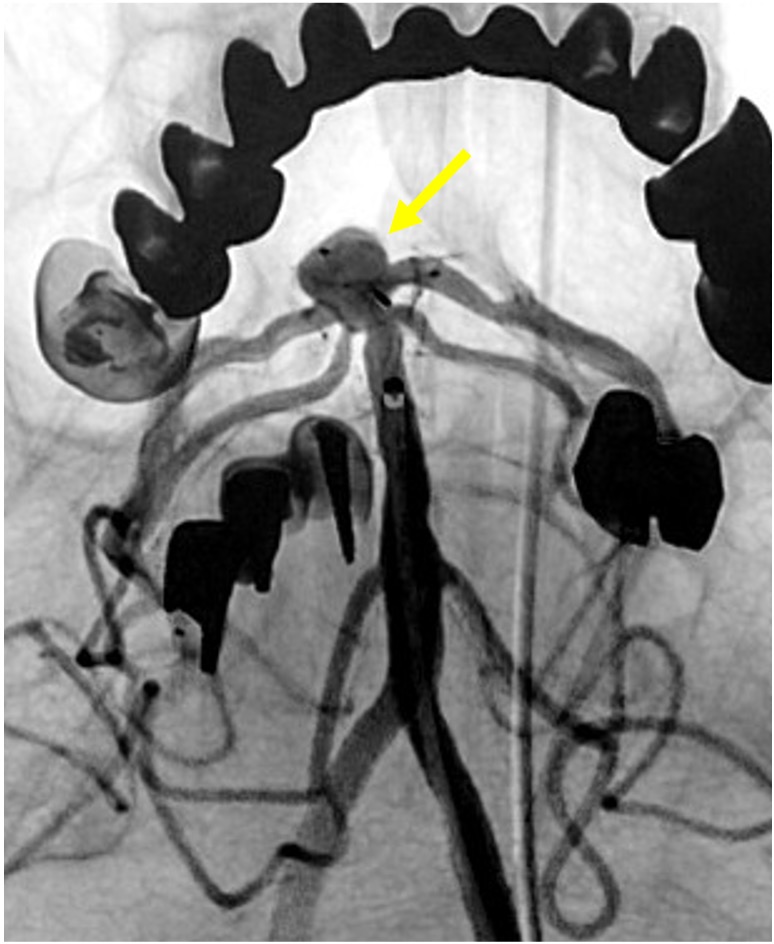

当院で行われた症例を提示いたします。80歳、女性、くも膜下出血の患者様。血管撮影にて図1〜4赤矢印の様に脳底動脈に広頸のネックを伴う不整形の瘤を認めました。母血管の蛇行狭窄が強く、マイクロカテーテルが複数入りにくい状態だったのでWEB(図5〜8黄色矢印)を用いて治療を行いました。術後MRAでも図10青矢印の様に動脈瘤は描出されません(図9は術前MRA)。現在も出血なく経過しております。

![]() 図8 |